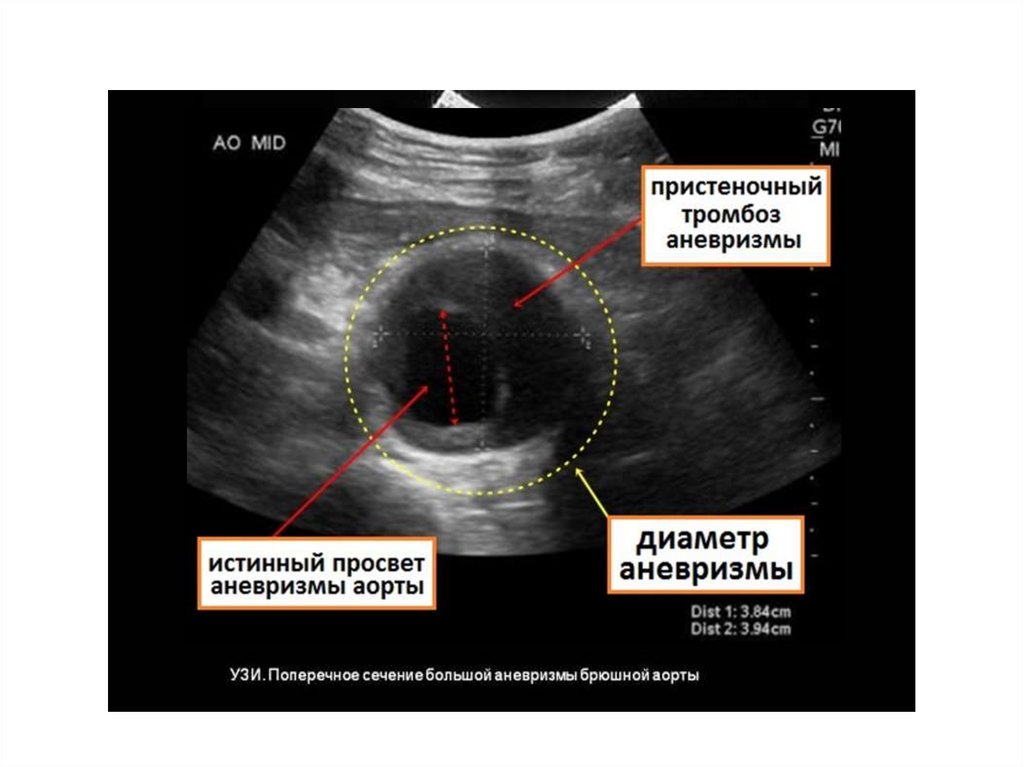

Диагностика АБА

аорты в 2 раза и более по

при коарктации аорты с анастомозом аорты конец в конец. О первой успешной резекции